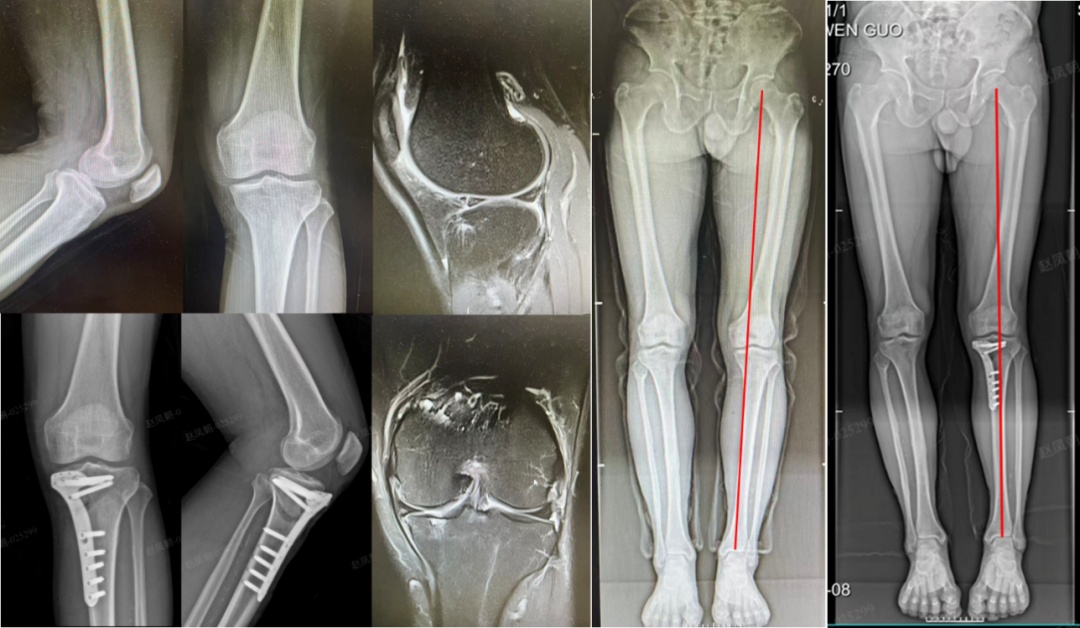

这项治疗主要适用于因膝内翻(“O”型腿)导致膝关节内侧过度负重、软骨磨损,但外侧间室健康的较年轻、活动量大的患者,也适用于内侧半月板后根损伤的病人。

技术精髓在于通过精确截骨调整小腿力线,如同为倾斜的房屋加固地基、纠正承重轴。核心优势在于保留全部自身关节,手术不切除任何关节结构,旨在通过力线矫正,从根本上缓解关节磨损进程。这为活跃的年轻患者争取更长的“原装关节”使用寿命,是真正意义上的“预防性”修复。